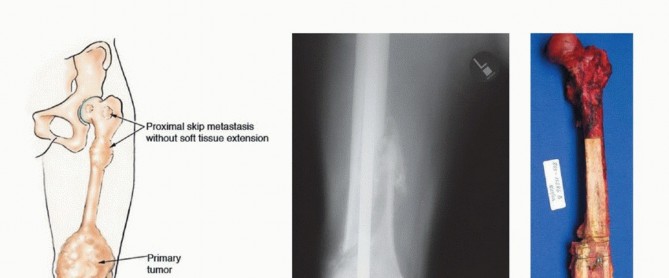

BACKGROUND The two most common primary malignant bone tumors, osteosarcoma and Ewing sarcoma, are principally…